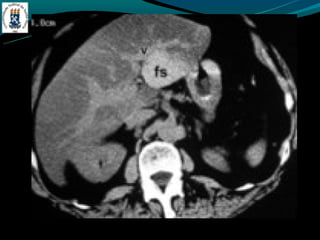

DOENÇA DO FÍGADO GORDUROSO

-E uma resposta uma lesão e a toxina

-Acúmulo de colesterol e triglicerídios

-Alcoolismo, obesidade, desnutrição, hiperalimentação,

costicóide, DM, pancreatite …

-Exames de imagem é o melhor método

-Avaliação:

-   TC: densidade menor do que do baço

-   RM: identificar esteatose focal

-Esteatose focal

-   Distribuição segmentar, sub capsular, VB, lig falciforme

-   Margem nítida e em linha reta

-   Não desloca vasos

DOENÇA DO FÍGADOGORDUROSO -E uma resposta uma lesão e a toxina -Acúmulo de colesterol e triglicerídios -Alcoolismo, obesidade, desnutrição, hiperalimentação, costicóide, DM, pancreatite … -Exames de imagem é o melhor método -Avaliação: - TC: densidade menor do que do baço - RM: identificar esteatose focal -Esteatose focal - Distribuição segmentar, sub capsular, VB, lig falciforme - Margem nítida e em linha reta - Não desloca vasos